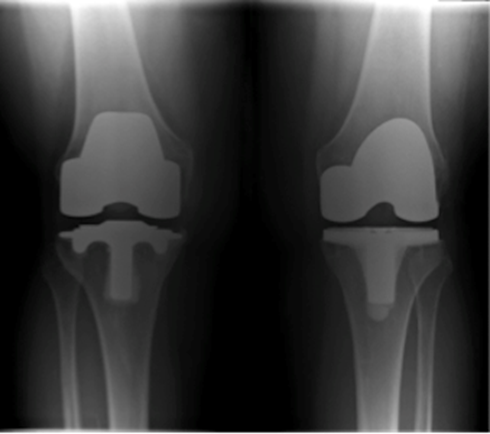

Knee Replacement

Revision Knee Replacement